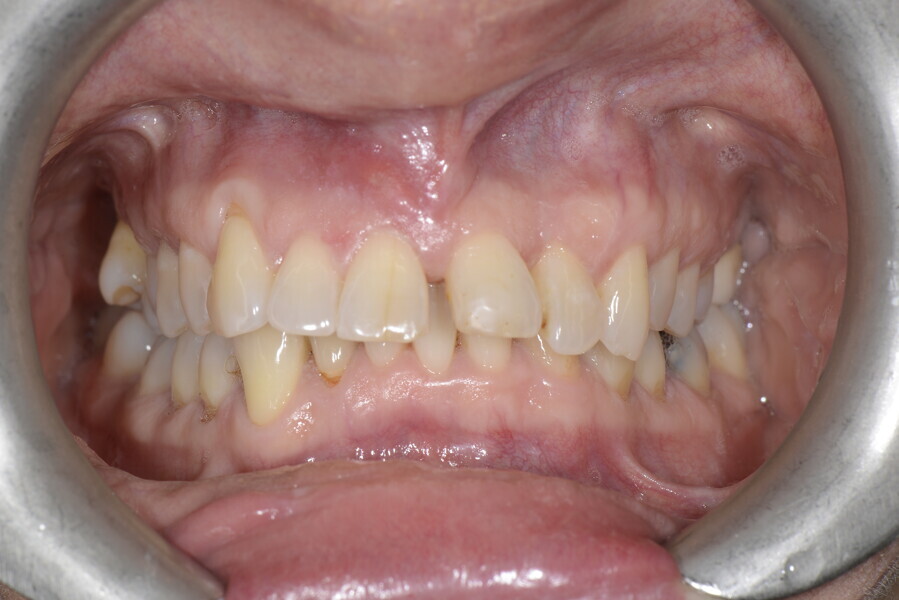

The 58-year-old patient wished to improve his oral aesthetics and function, complaining of mobility of the posterior teeth and wear of the anterior teeth. After data collection, a very complex situation was identified (Figs. 11–13):

1. severe periodontitis with poor prognosis of some teeth;

2. anterior crossbite;

3. severe wear mainly of the anterior teeth and compensatory eruption;38

4. atypical swallowing and lower posture of the tongue at rest;

5. masticatory dysfunction during the mastication test; and

6. no significant signs of temporomandibular disorder.